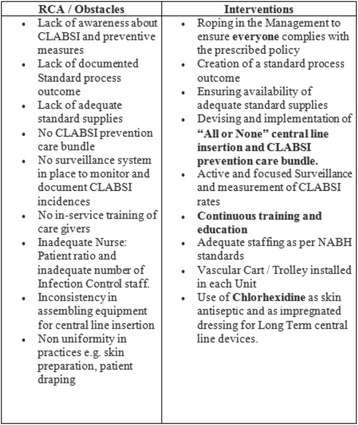

P059 - “Zero CLABSI” – can we get there? Obstacles on the 4 year journey and our strategies to overcome them – experience from an Indian ICU

V. Adora, A. Kar, A. Chakraborty, S. Roy, A. Bandyopadhyay, M. Das

P061 - Zero clabsi” – can we get there? Obstacles on the 4 year journey and our strategies to overcome them – experience from an Indian ICU

R. Rao, A. Kar, A. Chakraborty